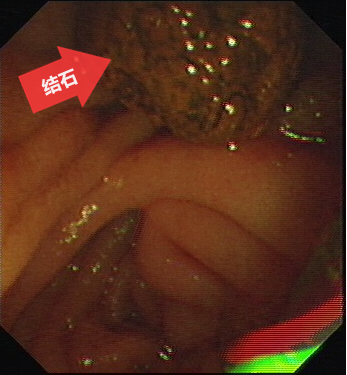

圖五:結石(箭頭所指)已取出至腸腔。

第五步:用取石網籃將結石從膽總管內取出到腸腔,通過腸道排出體外。